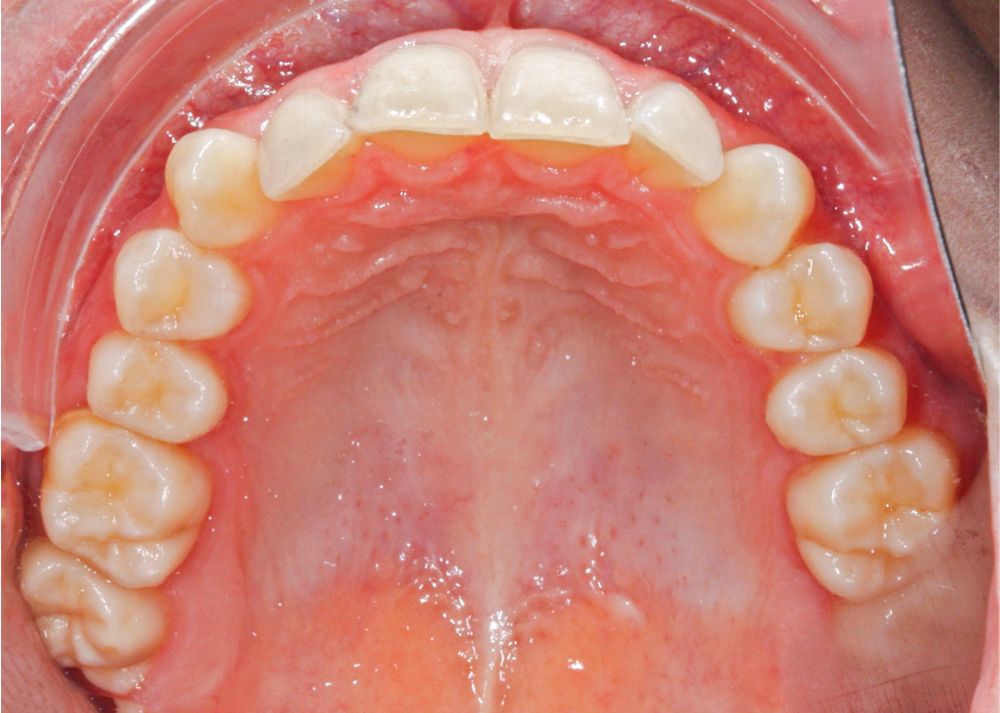

L’examen intra-arcade met en évidence une hygiène bucco-dentaire irréprochable, favorable à un traitement en technique linguale. Le phénotype parodontal est fin dans la région incisivo-canine mandibulaire. L’encombrement est estimé à 8 mm à la mandibule et à 4 mm au maxillaire (fig. 1). Les arcades ont des formes similaires, en U. Les rapports inter-arcades mettent en évidence une classe 1 d’Angle molaire, une classe 2 d’Angle canine et une supraclusion antérieure (recouvrement : 5 mm ; surplomb diminué). Les milieux inter-incisifs sont déviés entre eux avec une origine mixte (= 1,5 mm) (fig. 2).